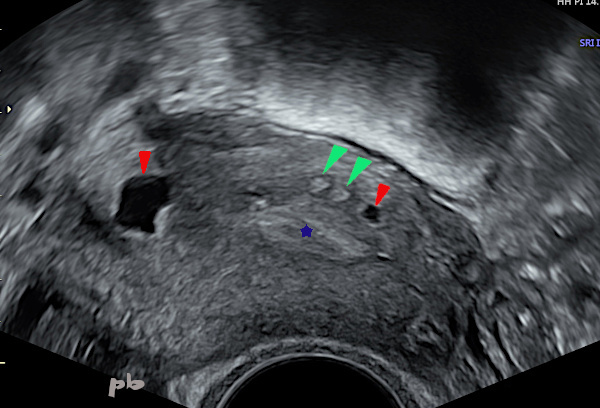

Présence de kystes anéchogènes (►) de taille variée, et hyperéchogènes hématiques (►), situés dans le myomètre, à proximité de l’interface endomètre- myomètre : adénomyose interne.

Endomètre (★).

Presence of anechoic cysts (►) of varying sizes, and hyperechoic hemorrhagic cysts (►), located in the myometrium, near the endometrium-myometrium interface : internal adenomyosis.

Endometrium (★).